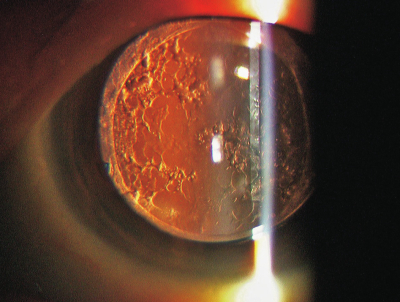

白内障手術後、2年経過して術眼の霧視を訴える患者の細隙灯顕微鏡写真(徹照像)を別に示す。認められるのはどれか。

d. 後発白内障